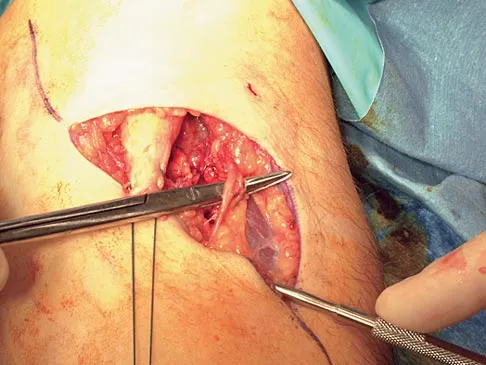

Question 67

A 45-year-old man sustains a low-velocity gunshot wound to the base of the right thumb. The open wound is allowed to heal by secondary intention, resulting in a contracture of the first web space. Clinical photographs are shown in Figures 49a through 49c. Treatment should now consist of